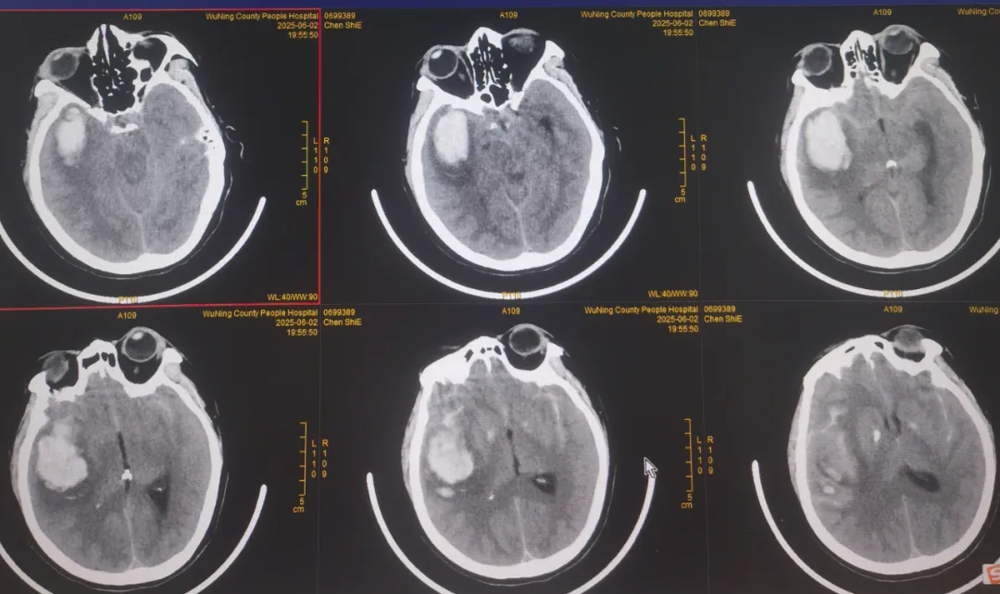

【填補縣域空(kōng)白】武寧縣總(zǒng)醫院人民醫院院區神經外科成功完成首例腦(nǎo)動脈瘤夾閉手術

近日,武寧縣總醫院(yuàn)人民醫院院區神(shén)經外科團隊順利完成了我縣首例破裂腦動脈瘤夾閉手術,患者術後情況良好,恢複(fù)效果理想。

腦動脈瘤夾閉借助高清晰顯微鏡下操作,手術難度高、風險大,以(yǐ)往(wǎng)此類患者隻能轉診(zhěn)上級醫院。人民醫院(yuàn)院區神經(jīng)外科團隊憑借紮實的(de)專業功底迎難而(ér)上,精準操作,成功拆除患者顱內"不定(dìng)時炸彈(dàn)"。這一突破填補了我縣(xiàn)在腦動脈瘤治療領域的技術(shù)空白。

近年(nián)來(lái),武寧(níng)縣總醫(yī)院人民醫院院區(qū)神經外科團隊借力與湘雅醫院江西醫(yī)院緊(jǐn)密(mì)型醫聯體東風(fēng),展現出蓬勃向上的發展勢頭,多項高難度診療技術日臻成熟:微創神經內鏡技術、顯微(wēi)鏡下腦內血腫(zhǒng)清除術、腦膜瘤切除術以及複雜重型顱腦創傷救治能力實(shí)現突破性(xìng)提升。此次腦動脈瘤夾閉手術成功實施,在縣域神經(jīng)外科(kē)領域(yù)書寫了新(xīn)的篇章,實現了“零”的突破。